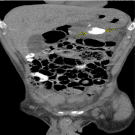

Ibrahim Farah, MD; Marwan Zaarab, MD; Juaquito M. Jorge, MD; Frederick M. Tiesenga, MD

A 51-year-old man presented to the emergency department (ED) with a 1-month history of abdominal pain, nausea, and non-bloody/non-bilious vomiting, which was associated with difficulty swallowing, decreased...